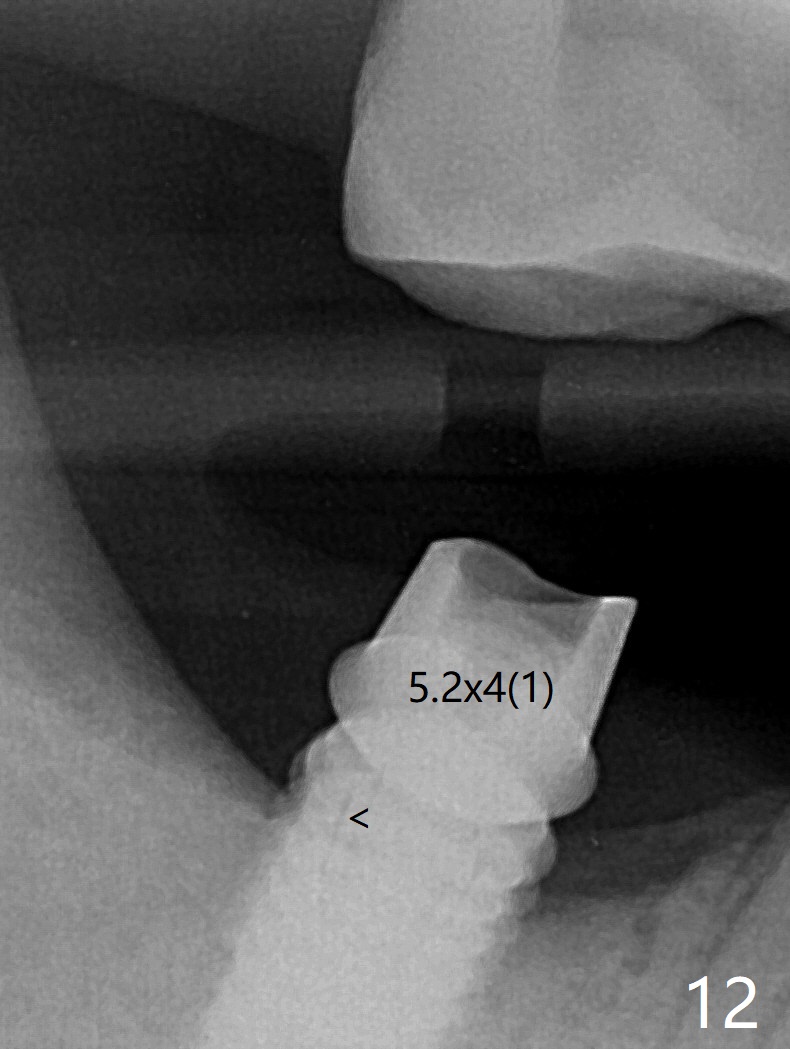

The residual roots of the tooth #31 are lower buccal (Fig.1 B), which in fact is molded and worn by the supraerupted tooth #2. When the tooth is extracted (Fig.2) and an implant, abutment (Fig.3 gold colored) and allograft (*) are placed, the abutment has to be trimmed. An atypical immediate provisional is fabricated by spreading setting acrylic over the abutment and bone graft (Fig.4 P) with occlusal equilibrium. Advantages of the guided surgery are good position (Fig.3 buccolingual), trajectory and depth (Fig.5,6) of the implant. The buccodistally exposed implant threads are packed with allograft in sufficient amount (Fig.3,5,6 *). The atypical immediate provisional breaks down and dislodges 3 weeks postop (Fig.7). In fact the implant plateau is exposed buccally. A monojet is given to the patient for self cleansing. He is instructed to return in 3 weeks. The exposed implant threads are covered 1.5 months postop (Fig.8). Incomplete abutment seating (Fig.9 <) was not noted until 1 year 3 month post cementation when the crown was mobile (Fig.10). A 6x3 mm healing abutment is placed. Three days later, the crown is sectioned and separated from the abutment. The latter returns to place; due to angulation associated with PA, the gap between the implant and abutment is indistinct (Fig.11). Bitewing is taken; the gap exists (Fig.12 <). The abutment seems to be seated deep; there is apparently soft tissue interference. A 5.2x4(2) mm abutment remains incompletely seated (Fig.13 >). A 5.2x4(3) mm one is completely seated (Fig.14 <). Zirconium crown with an access hole is cemented in the mouth. The crown and abutment is then removed for residual cement removal and reseated and torqued (Fig.15). Four months later, the Zirconium crown is fractured (Fig.16). Impression is retaken for high noble metal crown without access hole for strength (Fig.17).